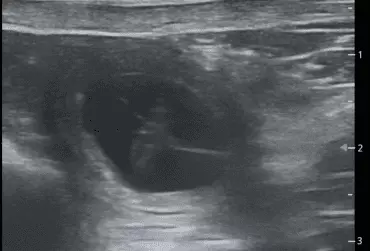

W literaturze opisano niewiele przypadków ciąż bliźniaczych jednokosmówkowych u suk. W trakcie wczesnej diagnostyki ultrasonograficznej ciąży u suki rasy whippet (chart angielski) zobrazowano pęcherz ciążowy, w którym znajdowały się dwa zarodki. Podczas badań kontrol­nych zarodki, a później płody wykazywały prawidłową organogenezę i żywotność. Ich rozwój przebiegał podobnie względem pozostałych ośmiu płodów. W 63. dniu ciąży wykonano zabieg cesarskiego cięcia i wydobyto dwa płody tej samej płci, o bardzo podobnym wyglądzie, z dwóch pęcherzy płodowych przyczepionych do jednego łożyska, oraz pozostałe osiem płodów.

Ryzyko związane z ciążą bliźniaczą jednokosmówkową u ciężarnych suk nadal jest nieznane, istnieją jednak doniesienia o śmierci płodu lub płodów w ciążach jednokosmówkowych u tego gatunku. Badanie ultrasonograficzne w czasie ciąży pozwala na wczesne rozpoznanie ciąży jednokosmówkowej, a monitorowanie żywotności płodów może ograniczyć ryzyko powikłań położniczych i przynieść korzyści zdrowotne zarówno samicy, jak i rodzeństwu z miotu.